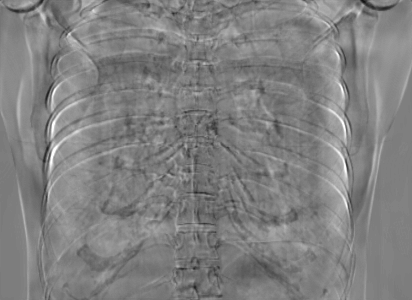

5.1 Chest Data

Refer to caption

(a) Reference

(b) 0superscript00^{\circ} perspective

(c) (b)-(a)

0.4237, -, -

0.4002, 17.01, 0.6532

Figure 10: Perspective deformation learning in one exemplary patient case for chest X-ray imaging. The maximal horizontal cardiac diameter and the maximal horizontal thoracic diameter in (b) and (d)-(f) are indicated by the horizontal red lines, while those in the reference image (a) are green lines. The cardiothoracic ratio, RMSE, and SSIM for each image is displayed in its corresponding subcaption.

The results of one patient in chest X-ray imaging are displayed in Fig. 10, where the cardiothoracic ratio is assessed as an exemplary clinical application [32]. In the reference image (Fig. 10(a)), the maximal horizontal cardiac diameter (MHCD) and the maximal horizontal thoracic diameter (MHTD) are indicated by two green horizontal lines. Its cardiothoracic ratio is 0.4237. In the 0superscript00^{\circ} perspective projection image (Fig. 10(b)), all the anatomical structures can be visualized with fine resolution. However, due to perspective deformation, anatomical structures, e.g. the ribs and the spine, are deformed. The deformations are visualized better in the difference image Fig. 10(c). Compared with the ribs and the spine, the heart has less deformation as its location is closer to the isocenter. In Fig. 10(b), the MHCD and the MHTD are indicated by two red horizontal lines, while the green lines are those of the reference image. While the MHCD has changed little from 10.47 cm to 10.16 cm, the MHTD has changed considerably from 24.71 cm to 25.40 cm. As a consequence, the cardiothoracic ratio becomes 0.4002, which is below the normal range of 0.42 - 0.50 [32]. The result of learning perspective deformation from 0superscript00^{\circ} single view is displayed in Fig. 10(d), where the MHCD and the MHTD are 10.63 cm and 24.71 cm, respectively. The MHTD of Fig. 10(d) is the same as that of the reference image. This is also reflected by the difference image Fig. 10(g), where the lower ribs have small errors. However, the upper ribs as well as the spine still have considerable errors. The results of perspective deformation learning from 0&180superscript0superscript1800^{\circ}\&180^{\circ} views in Cartesian and polar coordinates are displayed in Fig. 10(e) and Fig. 10(f), respectively. The measured MHCDs and MHTDs in these two images are very close to the reference ones. Hence, their cardiothoracic ratios, 0.4214 and 0.4240 respectively, are close to the reference ratio as well. In the difference images (Fig. 10(h) and Fig. 10(i)), the errors of ribs and spine decrease as their boundaries are no longer apparently visible. Nevertheless, Fig. 10(i) has less error than Fig. 10(h), achieving the smallest RMSE value of 3.83. The quantitative evaluation of all the 162 testing datasets is displayed in Tab. II, where learning perspective deformation from two complementary views in polar coordinates achieves the least RMSE 4.98 and highest SSIM 0.9517, demonstrating the superiority of learning perspective deformation from two complementary views in polar coordinates.